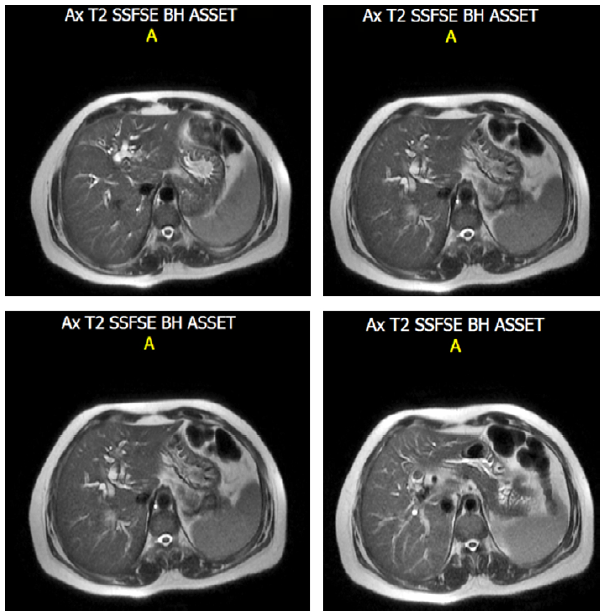

Fortunately, today surgeons can plan procedures in an optimal manner, since ultrasound has a performance close to 80 or 90%, and is sufficient in most cases. However, in a case such as the one presented here, in which a scleroatrophic vesicle, chronic cholecystitis and acalculous cholecystitis were identified - the latter using tomographic studies-, agenesis of the gallbladder cannot be disregarded. In these cases, other specialized methods such as MRC (Figure 2), endoscopic ultrasonography, ERCP, among others, can be helpful. 9.

MRC sequence in T2 of the bile duct. Note the absence of gallbladder.

Figure 2: MRC sequence in T2 of the bile duct. Note the absence of gallbladder.

Source: Own elaboration based on the data obtained in the study.